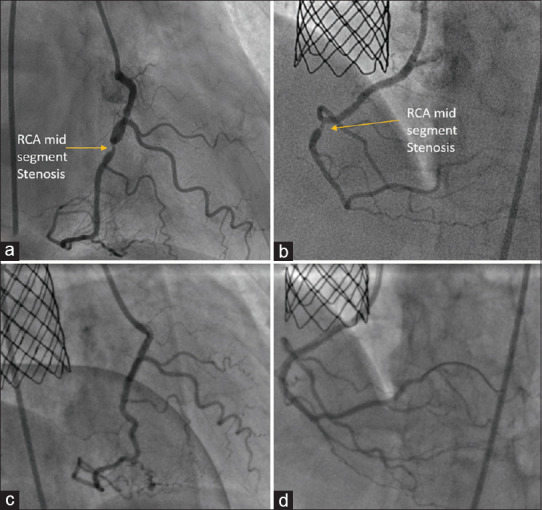

Superior vena cava (SVC) type of sinus venosus defect (SVD) associated with anomalous right upper pulmonary vein (RUPV) drainage is often corrected by open-heart surgery. Transcatheter-covered stent exclusion is an attractive emerging alternative using a covered stent in the lower end of SVC to close the SVD and redirect the RUPV to the left atrium. The location of SVD posterosuperior to oval fossa challenges its transthoracic echocardiographic identification and delays its diagnosis to adult age. Lifestyle adult diseases, including atherosclerosis, elevate the left ventricular end-diastolic pressures and increase the pretricuspid left-to-right shunt. Surgery addresses coronary stenosis and SVD, but lifestyle diseases increase surgical risks. We diagnosed significant coronary stenosis in three patients with SVD. These patients underwent percutaneous management of both lesions. Nonsurgical management of SVD and ischemic heart disease is a more viable alternative than a high-risk surgery in adults with comorbidities.